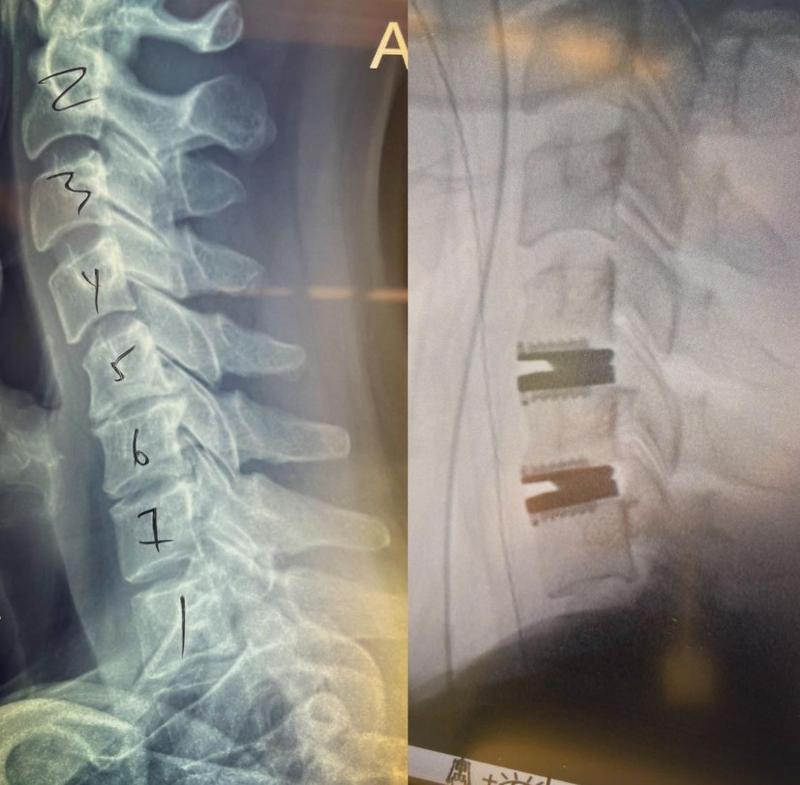

Actrița din „Aleea cu licurici”, serial care poate fi urmărit pe Netflix, a ajuns pe mâna medicilor din Los Angeles, după ce a suferit un accident. Heigl a trecut printr-o operație grea, în urma căreia i-au fost implantate două proteze de titan în locul unor discuri vertebrale uzate.

Într-un mesaj pe contul personal de Instagram, Katherine Heigl a povestit: „Ei bine, am devenit femeia bionică! Am două bucăţi de titan în gât, cred că aş putea să stau în cap ore întregi. Nu voi încerca asta chiar acum, dar daţi-mi câteva luni și vă voi lua mințile!”